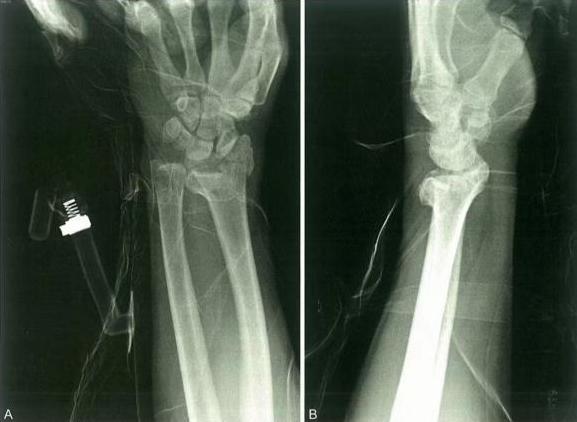

Primer ③